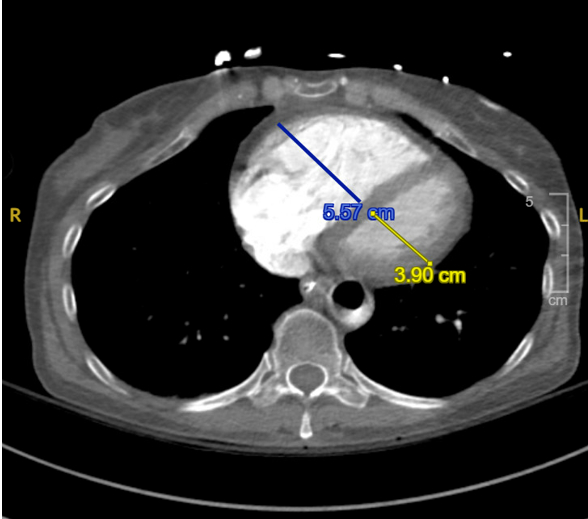

Abstract Body (Do not enter title and authors here): Case Presentation: A 53-year-old woman with a history of recent left patellar fracture and tobacco use presented with sudden-onset chest pain and shortness of breath. ECG showed ST elevations in II, III, and aVF with reciprocal depressions. CT angiography revealed a saddle pulmonary embolism with extensive bilateral emboli and right heart strain. Emergent coronary angiography showed 100% RCA occlusion - from proximal PDA through the AV groove. She was diagnosed with massive, high-risk PE and experienced progression from second- to third-degree AV block, which resolved after revascularization. Percutaneous coronary intervention was performed with successful RCA thrombectomy. She developed cardiogenic shock requiring norepinephrine and milrinone. The shock team placed an intra-aortic balloon pump (IABP). Ultrasound showed a non-occlusive thrombus in the left posterior tibial vein. Transthoracic echocardiogram on the following day of hospitalization showed normal LVEF (60–65%), RV dilation, septal flattening, and severely reduced RV systolic function. A bubble study confirmed a patent foramen ovale with right-to-left shunting. Due to RV wall thinning and elevated pulmonary pressures, the Pulmonary Embolism Response Team recommended IR-guided mechanical thrombectomy. Post-procedure, the patient improved and was weaned off IABP, pressors, and ventilator support. At discharge, she was started on a direct oral anticoagulant. One-month follow-up TTE revealed normalized RV size, mild right atrial dilation, and preserved LVEF.